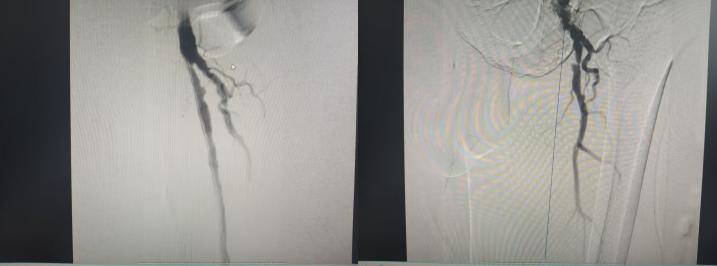

手术当天,在麻醉科等相关科室的全力配合下,专家团队凭借精湛的医术和默契的协作,有条不紊地开展手术,先后完成血管造影、机械取栓、球囊扩张等多项高难度操作。经过5个小时的全力奋战,手术圆满成功,全程没有出现任何并发症!

术后,王先生的左下肢疼痛缓解,皮肤温度明显回升,血管搏动也恢复了正常,肢体供血得到了有效改善,困扰他多日的病痛彻底解除。